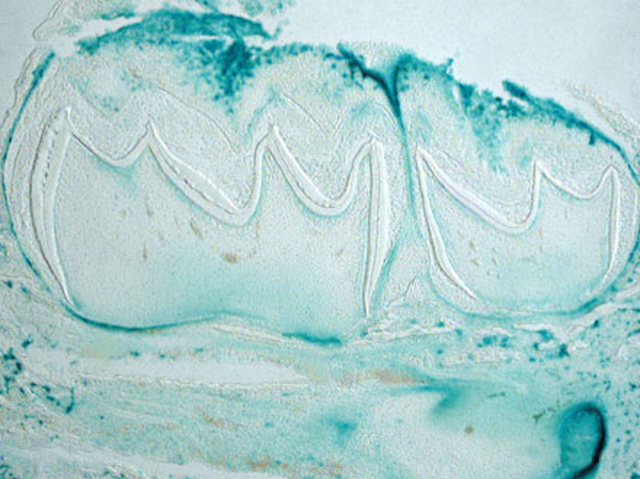

Beyond the hard white business end (crown) we may not give much thought to what makes up our teeth. When they form, the root and crown develop separately. Cells already in position in the jaw create each two-layered root – dentin on the inside and cementum on the outside – but nobody knew which cells they were. Now, in mice, researchers have identified a group of cells bearing an active osterix gene, which make both layers. To complete their development a series of genes, including PTHrP, become active in these root cells. If PTHrP is stopped from working, teeth have much shorter roots and don’t erupt from the gums. Pictured are developing teeth, with the cells containing active PTHrP stained blue in a dense line at the under surface where the root will form. The next step is to figure out the role of PTHrP, and what other genes are involved.